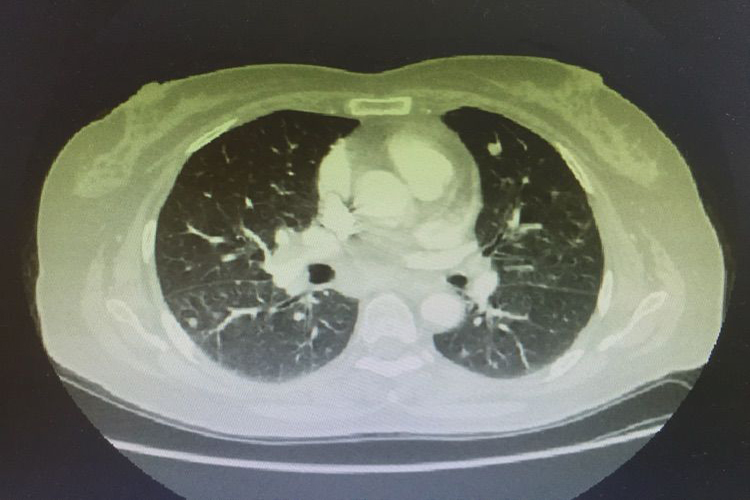

血行转移:肾细胞癌先侵犯肾静脉,导致静脉内形成癌栓,还可向远处转移到肺、肝、骨骼等处。